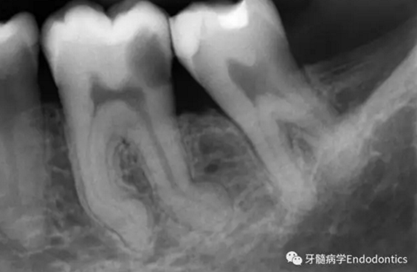

圖2.疏通根管冠方2/3后,使用次氯酸鈉溶液沖洗根管,且可以使用手用器械、GG鉆(刷洗動(dòng)作)、旋轉(zhuǎn)鎳鈦成形銼預(yù)敞根管。當(dāng)冠方2/3進(jìn)行了合適的預(yù)備且充滿沖洗液后,接著進(jìn)行根尖1/3的探查以收集信息。使用小的手用銼(8號(hào)或10號(hào)K銼)疏通根管的剩余部分,確認(rèn)建立了流暢的、無阻礙的、平滑的到達(dá)根尖止點(diǎn)的引導(dǎo)通道。

圖3.存在細(xì)小狹長(zhǎng)、可能多維的復(fù)雜根管解剖時(shí),使用10號(hào)K銼不可能立即疏通根管到達(dá)根尖止點(diǎn)。隨后醫(yī)生應(yīng)嘗試使用更小的銼探查以達(dá)到根尖。但是,通常不需要使用6號(hào)和8號(hào)K銼對(duì)到達(dá)根尖的引導(dǎo)通道進(jìn)行擴(kuò)大,除非是特別困難的病例。